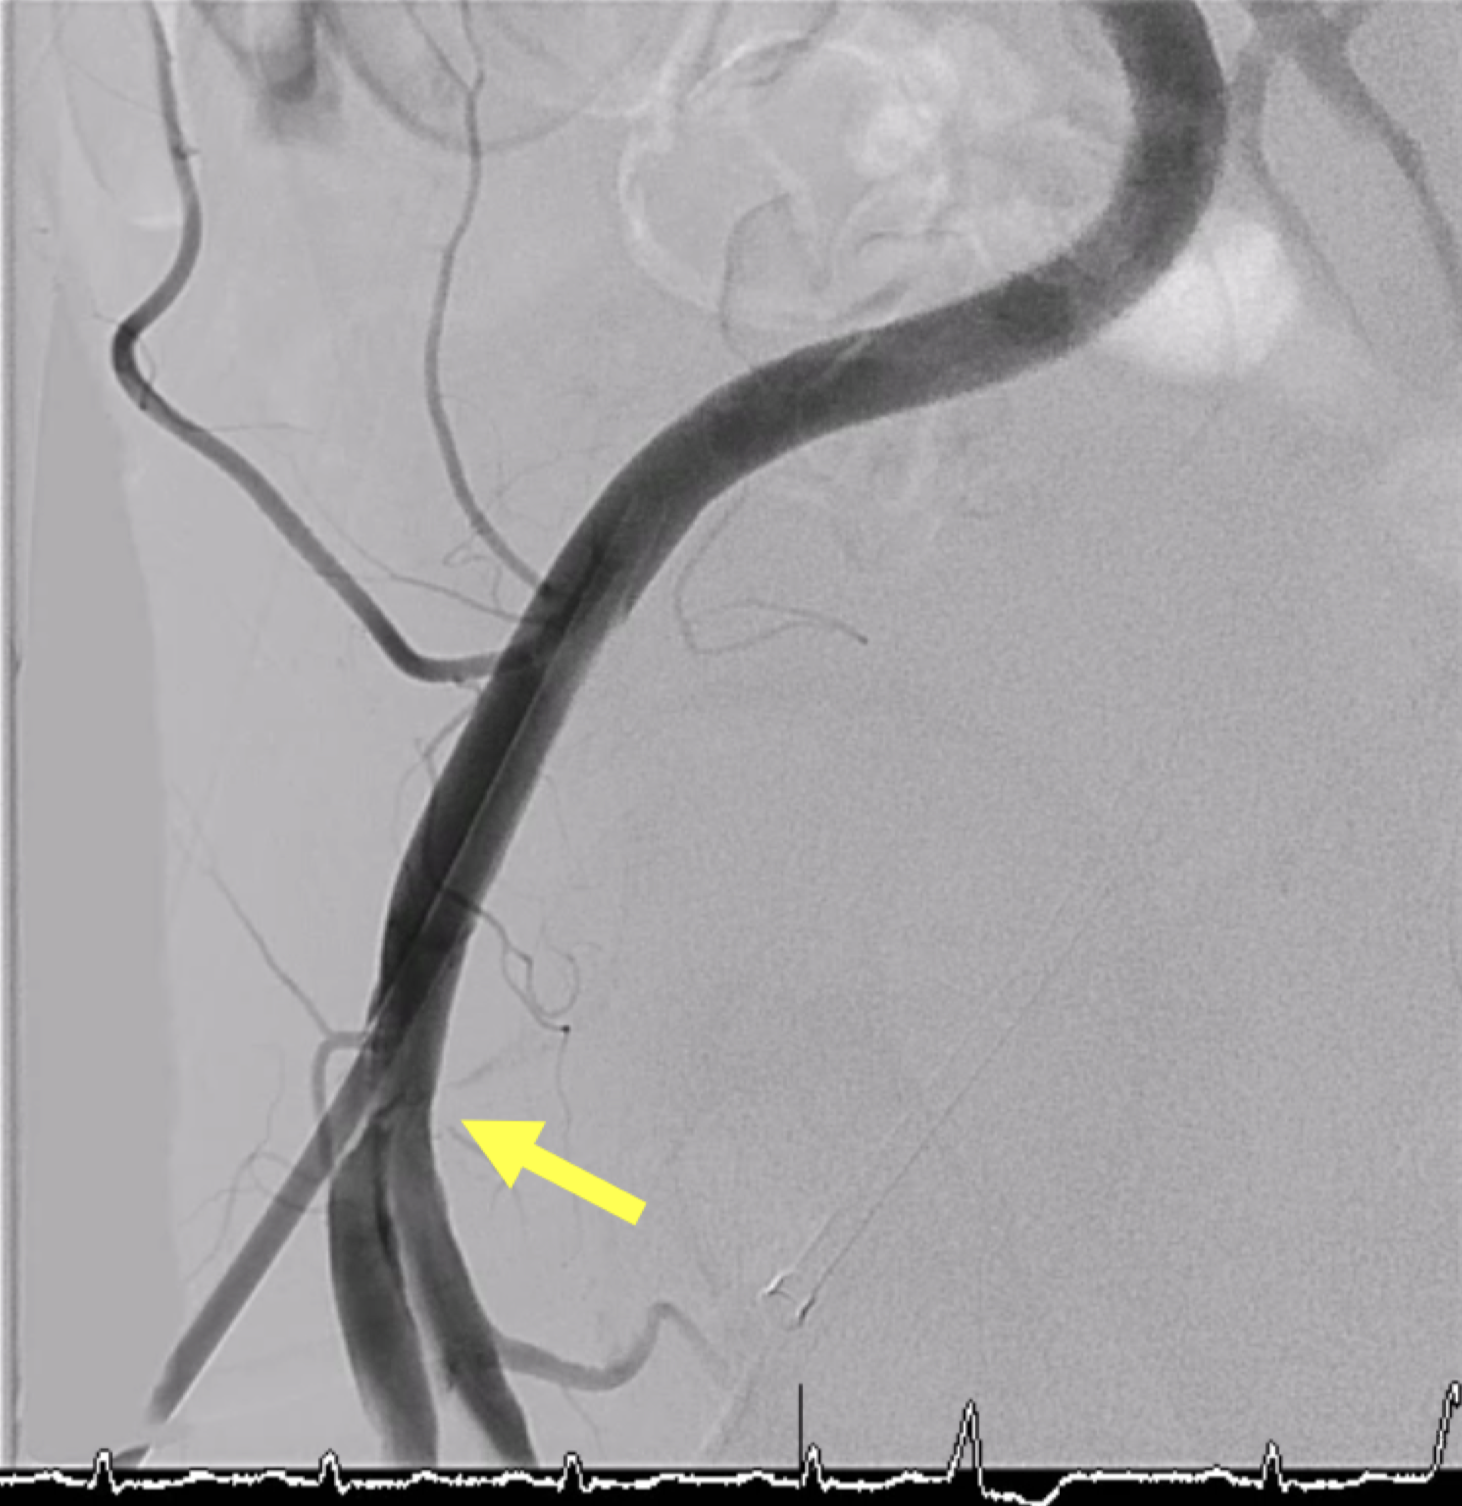

- LM: Bifurcation lesion (medina 0, 1, 1) - LAD: Ostial stenosis 80 %, proximal stenosis 90%, middle stenosis 70 %, with collateral to LCx and RCA - LCx: Ostial stenosis 80 %, proximal stenosis 70 %, distal CTO, with collateral to RCA - RCA: Proximal stenosis 50 %, middle CTO, with intracoronary collateral - Syntax score: 37.5 - Right SFA: arterial sheath in situ with an iatrogenic AV fistula

Procedural Step

Vascular duplex was performed instead of CT for large-bore access evaluation due to acute kidney injury, revealing severe stenosis of the left common femoral artery. Despite this, an Impella CP¢ç sheath was successfully inserted using contralateral injection and fluoroscopic-guided puncture, and the device was advanced into the left ventricle uneventfully. Initial hemodynamic data from the pulmonary artery catheter showed elevated pulmonary artery wedge pressure (32 mmHg), pulmonary hypertension (68/22 mmHg, mean 43 mmHg), and a low cardiac index (1.98 L/min/m©÷) without vasopressors or inotropes. The wedge pressure decreased to 23 mmHg after Impella insertion, demonstrating effective hemodynamic support. A Medtronic 8 Fr EBU 3.5 guiding catheter with a side hole was used to engage the left coronary artery. IVUS of the LAD and LCx showed diffuse mixed calcified and fibrotic plaques with similar luminal diameters from the ostium to the proximal segments. Based on these findings, an upfront two-stent Culotte strategy was adopted. Both ostial-to-proximal LAD and LCx were pre-dilated with 3.0 mm balloons, followed by successful deployment of 3.0 ¡¿ 23 mm and 3.0 ¡¿ 28 mm drug-eluting stents to the LCx and LAD, respectively. The proximal-to-mid LAD and diagonal branch were also treated. After stent implantation, the patient was weaned smoothly from Impella, with pulmonary artery wedge pressure mildly elevated (23 mmHg after insertion and 25 mmHg post-procedure).